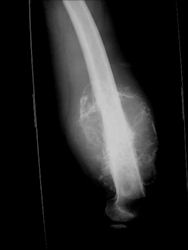

Radiographic Presentation: Conventional Osteosarcoma

There are 3 radiographic presentations for osteosarcomas, depending upon the amount of osteoid/ossification and calcium deposition:

- Mixed sclerotic and lytic, permeative lesion most common radiographic presentation

- Purely osteoblastic, permeative lesion: dense sclerosis and osteoid production

- Purely lytic, permeative lesion: little osteoid production and/or minimal calcium deposition in osteoid

Conventional osteosarcomas are permeative lesions on plain radiographs (borders of the lesion cannot be clearly delineated)

- Wide zone of transition from lytic/sclerotic areas of tumor to normal bone

- Makes borders of lesion hard to define

- Most (90%) arise from the metaphysis of the bone

- Rarely (10%) arise from the diaphysis

- Most conventional osteosarcomas (90-95%) extend through the bone into the soft tissues and form a soft tissue mass outside of the bone